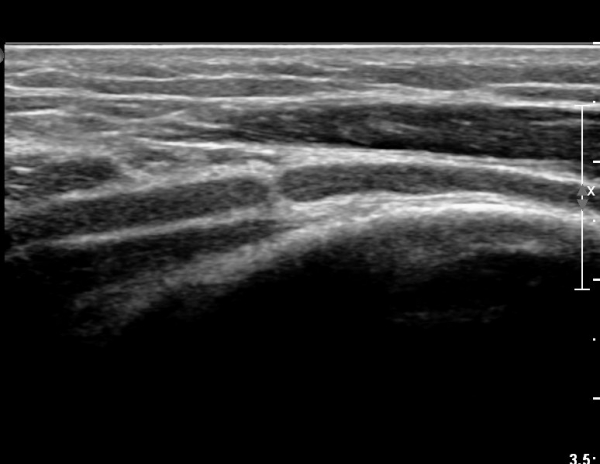

ŽÃÊÀÚ¸¦ Á¶±Ý ´õ ¸»´ÜÀ¸·Î À̵¿ÇÏ´Ï ¿ä°ñ½Å°æÀÌ °üÂûµÇÁö ¾Ê°í(»çÁø3),